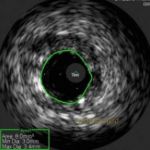

IVUS (Intravascular Ultrasound)

Learn more